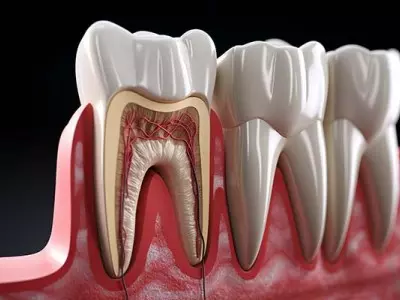

W tym wydaniu m.in: polerowanie i wygładzanie szkliwa i kompozytu, zasady wypisywania recept stomatologicznych, leczenie endodontyczne zębów stałych z niezakończonym rozwojem korzeni, rozwiązania w leczeniu rotacji zębów.